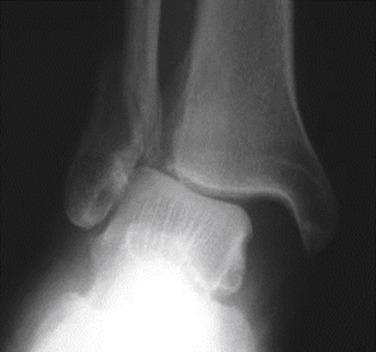

• It is important to understand that Charcot ankle fractures are uniquely different in that treatment requires more robust fixation and longer protected weight bearing than is typically required. The bone is softer due to increased resorption relative to new bone formation, and patients lack protective sensation allowing weight bearing on the fractured ankle ( Fig. 62.1 ). Failure to recognize these principles ( Fig. 62.2 ) risks failure due to loss of fixation ( Fig. 62.3 ), with subsequent revision ( Fig. 62.4 ), malunion and/or nonunion, and possibly amputation.

FIG. 62.1, (Courtesy Arthur Manoli)